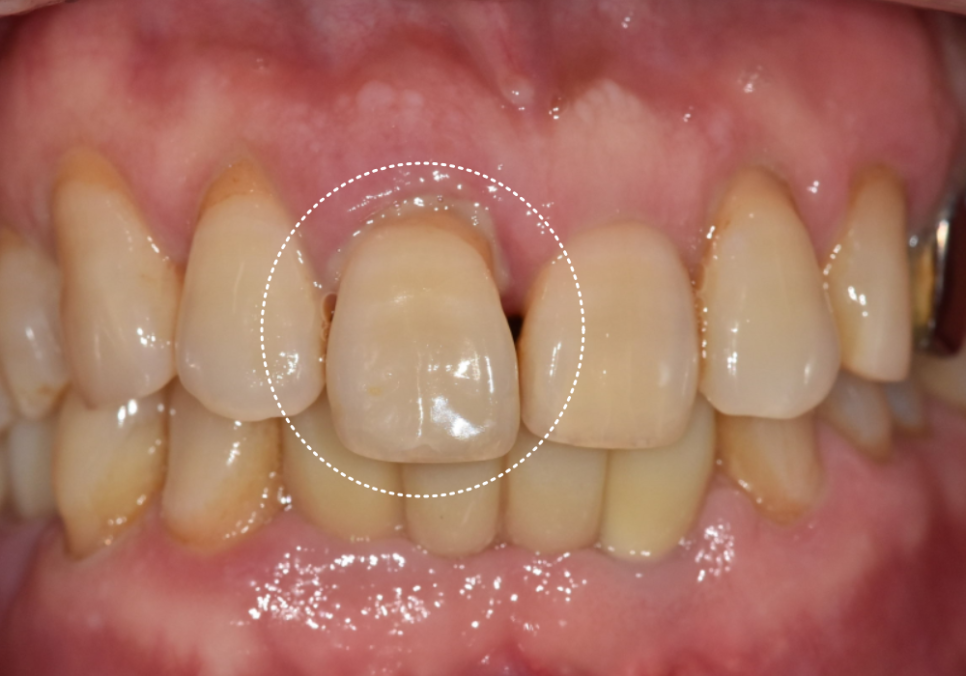

얼마 전 저희 치과를 찾으신 환자분의 사례예요.

위에 앞니 하나가 자꾸 내려와서 보기 싫고

무엇보다 흔들림이 심해 내원하셨어요.

입안을 살펴보니 위 가운데 앞니(#11)가

옆 치아들에 비해 확연히 아래로 내려와 있었어요.

그러다 보니 치아가 삐뚤어 보이는

느낌이 드는데요~

임플란트 식립 후 약 2달간 뼈와 임플란트가

단단하게 한 몸이 되기를 기다렸습니다.

이후 정밀 스캐너로 본을 떠서

주변 치아와 조화를 이루는

최종 보철물을 완성해 드렸어요.

짠! 어떠세요?

전이랑 비교했을 때

확실히 치아가 짧아 보이지 않나요?

옆 치아의 길이와도 대칭을 이뤄

자연스럽게 제작해 드렸답니다!